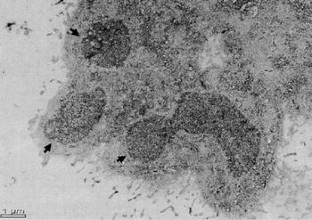

This work was supported by grants from COECyT-UMSNH (CB0702112_9 and CB0702138_1) and CONACyT (46400) to A.O.Z. and J.E.L.M. The authors thank to Dr. Alfonso Cárabez-Trejo (Neurobiology Institute, UNAM, México) for the electron microscopy micrographs and to Francisco Jesús Hidalgo Cervantes for the milk collection.